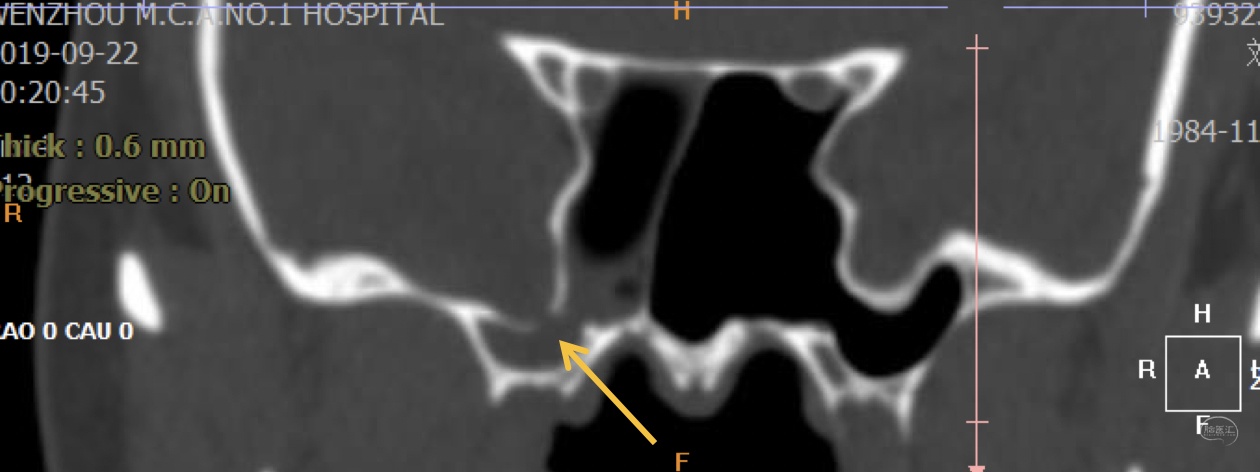

本次术前MRI

诊断:右侧蝶窦外侧隐窝脑膜脑膨出伴脑脊液漏。

病因分析:患者蝶窦过度气化,一直延伸至翼突,形成蝶窦外侧隐窝,造成中颅窝底出现薄弱区。患者第一次手术前因为松果体肿瘤,造成严重脑积水,颅内压明显增高,促使脑膜脑组织自颅底薄弱区疝出。但第一次手术术前并无脑脊液漏,而术后才出现脑脊液漏,可能的原因是:术前脑积水,造成颅内压较高,增高的颅内压一方面促使脑膜脑膨出,另一方面也迫使脑组织堵塞住了漏口,因而未出现脑脊液漏,手术后肿瘤全切除,脑积水缓解,颅内压下降,使得脑组织的堵塞漏口的作用下降,因此反而出现了脑脊液漏。

手术方案:内镜经鼻经翼突入路